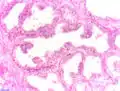

Adénocarcinome prostatique

Adénocarcinome ; tissus indifférenciés

Invasion périneurale par un adénocarcinome prostatique. HE, x400

Anatomopathologie

Le cancer entreprend la portion périphérique de la glande, au contraire de l'hypertrophie prostatique bénigne qui intéresse la zone centrale, périurétrale.

La gravité de l'évolution est corrélée avec l'aspect microscopique (score de Gleason), le niveau de PSA et l'extension de la maladie[53].

Score de Gleason

La structure tissulaire des cancers de la prostate varie des formes différenciées (cellules cancéreuses ressemblant aux cellules saines), dite de grade 1, aux formes les moins différenciées (cellules cancéreuses présentant beaucoup de caractères atypiques par rapport aux cellules saines), dite de grade 5.

Plusieurs grades peuvent se rencontrer au sein d'un même tissu. Le score de Gleason est calculé de la façon suivante : on additionne les deux grades les plus représentés de la tumeur. Le premier chiffre représentant le score du contingent le plus représenté. Ainsi 4+3 est plus péjoratif que 3+4

Si la somme est de 6 ou moins, le cancer est dit bien différencié, donc de meilleur pronostic ; 7 : le cancer est moyennement différencié ; 8 ou plus : le cancer est peu différencié, donc de moins bon pronostic.